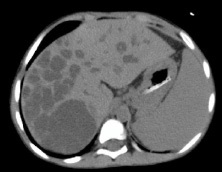

Laboratory examination showed anemia, cholestasis, hypoalbuminemia, prolonged of clotting time, elevated transaminase, elevated of gamma GT, dyslipidemia, vitamin D deficiency and positive CMV antigenemia. A doppler abdominal ultrasound was performed, which revealed intrahepatic multiple cysts, hepatomegaly with the appearance of liver fibrosis and signs of portal hypertension. From abdominal magnetic resonance imaging (MRI) with contrast showed choledochal cyst type V (according to Todani’s classification) (Figure 1) and biliary atresia (possibly type I), left kidney hypoplasia with multiple cysts, and hepatosplenomegaly.

Figure 1: Abdominal MRI with contrast.